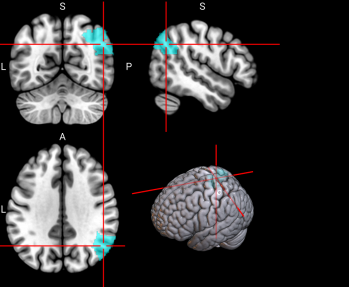

71,

72

L & R Precuneus (PCUN)

The precuneus is involved in recollection and memory, perception, episodic memory, and other cognitive processes [67].

/word/media/image16.png/word/media/image16.png